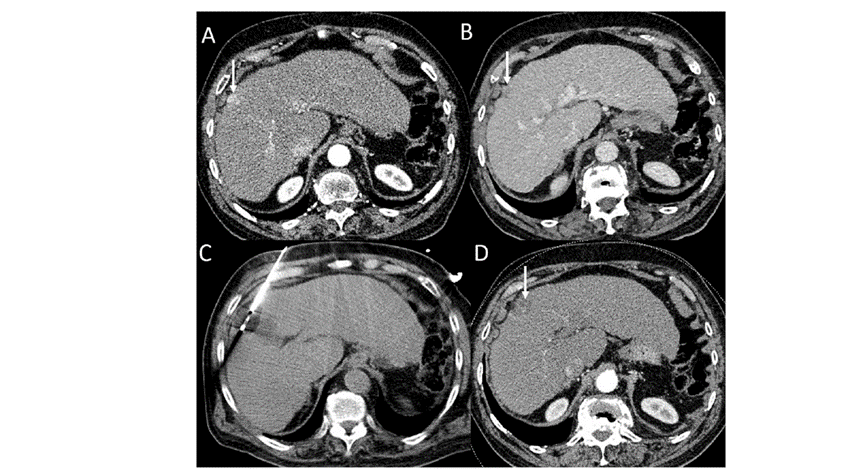

(A)動脈期CT圖像顯示有一個包膜下結(jié)節(jié)(箭頭)。(B)門靜脈期CT圖像顯示病灶區(qū)(箭頭)。(C) 在手術(shù)過程中的CT顯示一個冷凍探針位于病灶內(nèi)。(D)消融后,術(shù)后1個月影像CT顯示完全消融。患者在手術(shù)及住院期間無并發(fā)癥及重大并發(fā)癥發(fā)生。隨訪時間中位數(shù)為7個月(范圍:3-12個月),隨訪期間患者無局部腫瘤進展或死亡。

技術(shù)成功率為100%,本研究中77.8%(7/9)的患者達到了完全消融,輔助局部治療后,所有患者均完全消融。

膽囊附近轉(zhuǎn)移灶(來自子宮頸癌)的冷凍消融術(shù)(A)門靜脈期 CT 圖像顯示膽囊附近有病變(箭頭)。(C) 手術(shù)過程中CT 顯示冷凍探針位于病灶內(nèi)。(D)消融手術(shù)后 1 個月CT 顯示完全消融。

本研究中患者隨訪期間無局部腫瘤進展,無死亡病例,沒有發(fā)現(xiàn)與手術(shù)相關(guān)的并發(fā)癥。證實冷凍消融是一種有效的治療方式,在技術(shù)上是可行和安全的。由于肝包膜下病變位置特殊,射頻消融有出血及腫瘤種植的風(fēng)險,可能會對鄰近器官造成損傷,并且增加局部腫瘤進展的風(fēng)險。近年來,冷凍消融術(shù)的應(yīng)用逐漸廣泛,有研究顯示冷凍消融治療具有明顯優(yōu)勢,可治療特殊部位的肝腫瘤。本研究的目的是評價冷凍消融治療肝包膜下腫瘤的安全性和有效性。回顧性納入2016年7月1日至2018年9月1日期間冷凍消融的57例患者。包括42例男性和15例女性,平均年齡為62.4歲(范圍:48-82歲)。每個患者有1個或2個平均腫瘤尺寸為2.4cm的病變(范圍:0.6-4.0cm)。所有患者均患有慢性肝病或肝硬化,并伴有乙型肝炎(n=52)、丙型肝炎(n=3)和其他肝炎(n=2)。根據(jù)腫瘤位置,在膈肌或肝臟下附近有18個病變(26.5%),胃或腸附近有9個病變(13.2%),腹壁附近有33個病變(48.5%),腎臟附近有8個病變(11.8%)。